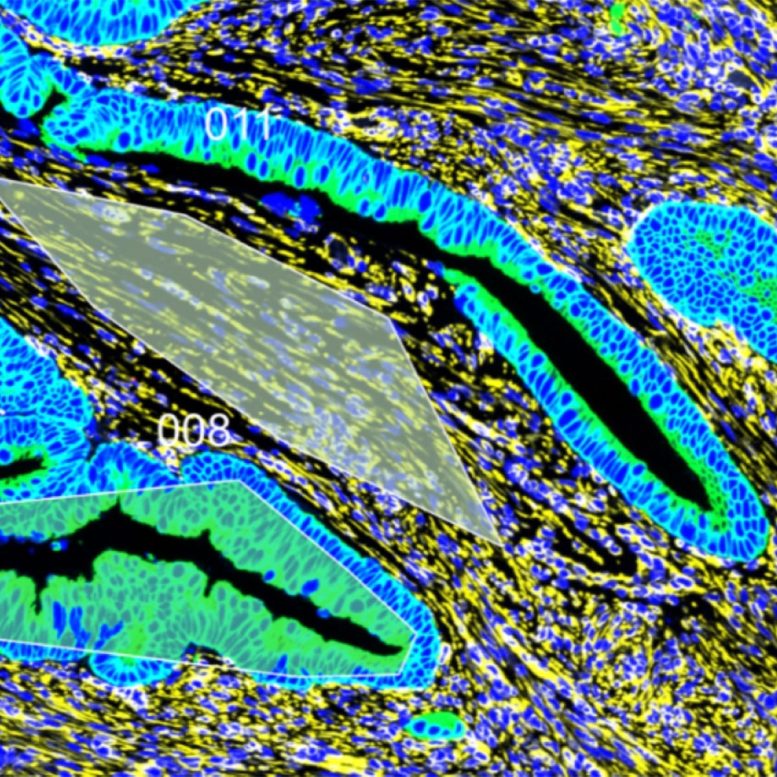

To answer this question, researchers worked with intestinal tissue from patients who underwent surgery to remove their cancerous tumors at William P. Clements University Hospital and Parkland Health: 19 samples from patients with average-onset CRC and 14 from patients with early-onset CRC. Each sample included not only malignant tumors but also their noncancerous margins. Tests showed that both the tumors and the noncancerous tissue were significantly stiffer in samples from patients with early-onset CRC compared with those from patients with average-onset CRC. These findings suggest that an increase in stiffness may have preceded early-onset CRC development.

Searching for a reason for this increased rigidity, researchers examined the collagen in both sample types, a protein that increases in abundance and changes conformation with scarring. They found that collagen in the early-onset samples was denser, longer, more mature, and more aligned than those in the average-onset samples. Those factors underscore the role of scarring in early-onset CRC tissue.

When scientists compared gene activity in the two sample types, they saw a significant increase in the expression of genes associated with collagen metabolism, blood vessel formation, and inflammation in the early-onset CRC tissues, further reinforcing that scarring from chronic inflammation is responsible for tissue stiffness. Importantly, they also noticed an uptick in a molecular pathway responsible for mechanotransduction, a process in which cells convert mechanical forces into biochemical signals. This suggests that cells in the early-onset CRC samples might change their behavior based on the stiffness of their environment.